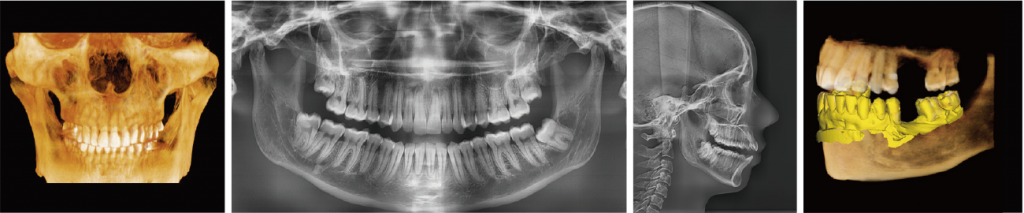

Томограф Vatech Green X (FOV18*15) - позволяет получить широкий спектр диагностических исследований КЛКТ (захват практически всего черепа) + ОПТГ + сканирование гипсовых моделей.

Новейшая цифровая рентгеновская система визуализации 4-в-1

Green X предлагает ряд переключаемых полей обзора. Выбор размера поля обзора позволяет пользователю подобрать оптимальный режим сканирования и уменьшает облучение областей, не входящих в зону интереса.

Выберите необходимый размер поля среди от 4х4см до 18х15 см, руководствуясь конкретными задачами диагностики. Аппарат подходит для диагностики полных зубных рядов, синусов, левого/правого ВНЧС и большинства случаев челюстно-лицевой хирургии. Также возможно измерение объема дыхательных путей.